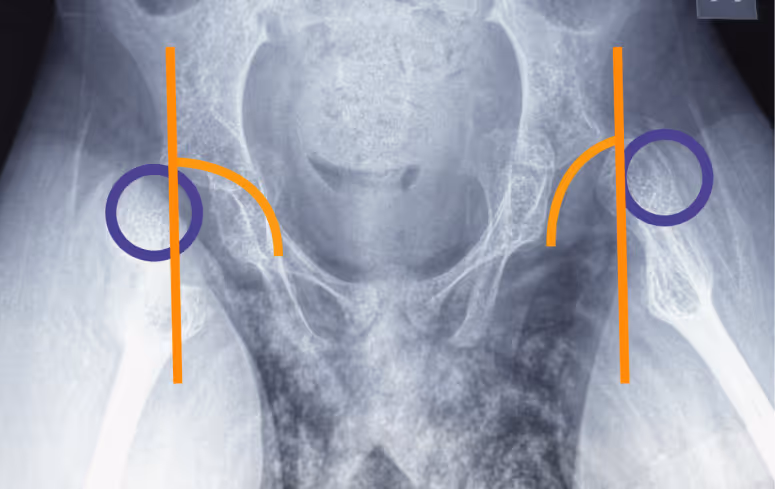

Диагноз ставит врач на плановом осмотре. Не все изменения в тазобедренных суставах можно увидеть на УЗИ, поэтому пациентам со СМА рекомендуется делать рентгенографию — по снимку врач определяет состояние суставов и решает, какие меры принимать.

Небольшое смещение головки бедренной кости, подвывих, полный вывих — все эти изменения ещё называют дисплазией тазобедренного сустава.